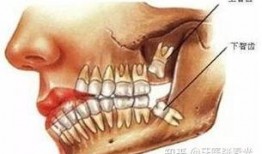

智齿完整版在线观看,揭秘青春成长的秘密与挑战

亲爱的读者们,你是否曾经好奇过,那颗隐藏在口腔深处的智齿,究竟是个怎样的存在?今天,就让我带你一起揭开智齿的神秘面纱,让你全面了...